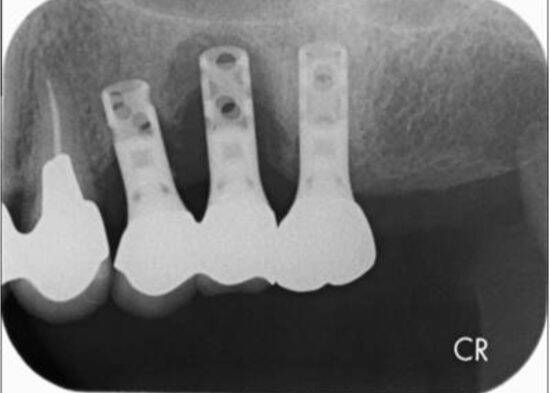

何年か前に入れたインプラントが揺れていると来院された患者さんがいました。レントゲン写真を撮ると、インプラントの周りが溶けて黒く写っています。

インプラント周囲炎とは、インプラントを支える歯茎や骨などの周囲の組織が炎症を起こす病気で、ひどくなるとせっかく埋入したインプラントが抜け落ちることもあります。

残念ながら、このケースもインプラントを抜くという選択になりました。